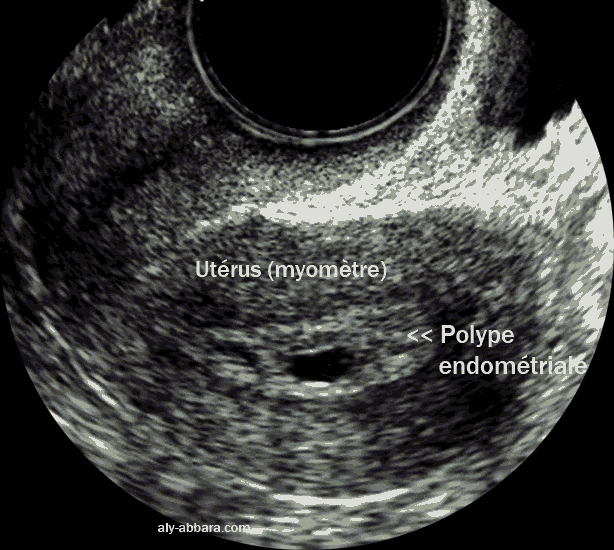

Polype endométrial chez femme de 58 ans, menopausée

Polype endométrial chez une femme âgée de 58 ans, ménopausée

et sans traitement hormonal oestroprogestatif.

L'aspect échographique évoque le diagnostic d'épaississement de l'endomètre (mesuré à 8 mm), mais l'hystéroscopie montre qu'il s'agit d'un polype endométrial de 5 cm de grand axe, aplati, en particulier au niveau de son extrémité inférieure ; il épouse parfaitement la forme de la cavité utérine avec une insertion pédiculaire peu large au niveau du fond utérin et de la corne droite. L'endomètre est par ailleurs, atrophique et quasiment inexistant

L'extrémité inférieure de ce polype est caractérisée par la présence d'une large zone d'hémorragie diffuse sous épithéliale ce qui explique les manifestations clinique chez cette patiente, à savoir, des métrorragies de faible abondance et intermittentes depuis quelques mois.